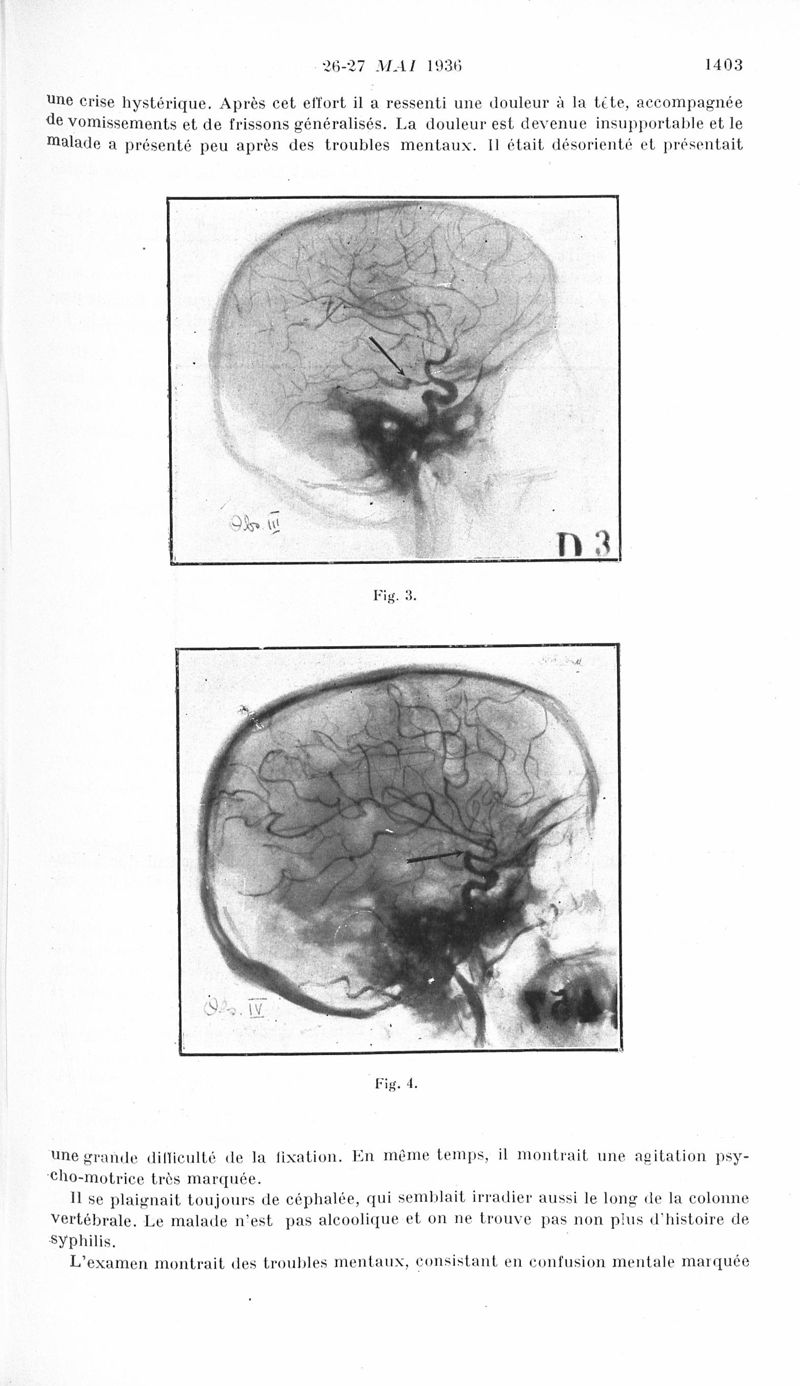

Revue neurologique

1936, vol 1. - Paris : Masson , 1936.